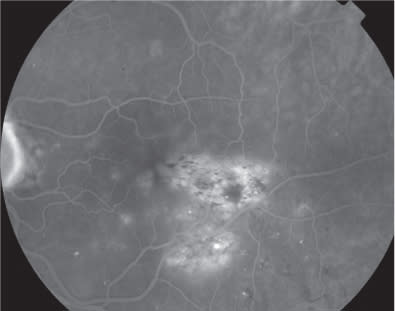

At baseline, best corrected visual acuity (BCVA) was 0.8 Snellen equivalent at right eye (RE) and 0.3 Snellen equivalent in the left eye (LE). Intraocular pressure was 14 mm Hg in both eyes. Slit-lamp examination of the anterior segment revealed nuclear sclerosis. Clinical examination of the retina revealed a nonproliferative diabetic retinopathy in both eyes, associated with the presence of clinically significant DME with hard exudative deposition in the LE (Figure 1). Central retinal thickness (CRT) on OCT was 223 μm and 551 μm in RE and LE, respectively, at baseline. Fluorescein angiography (FA) (Figures 2 and 3) disclosed more clearly the presence of the diabetic retinopathy with DME in the LE. The patient was advised to undergo intravitreal injection of ranibizumab.

Figure 1. Color photographs showing a clinically significant macular edema.